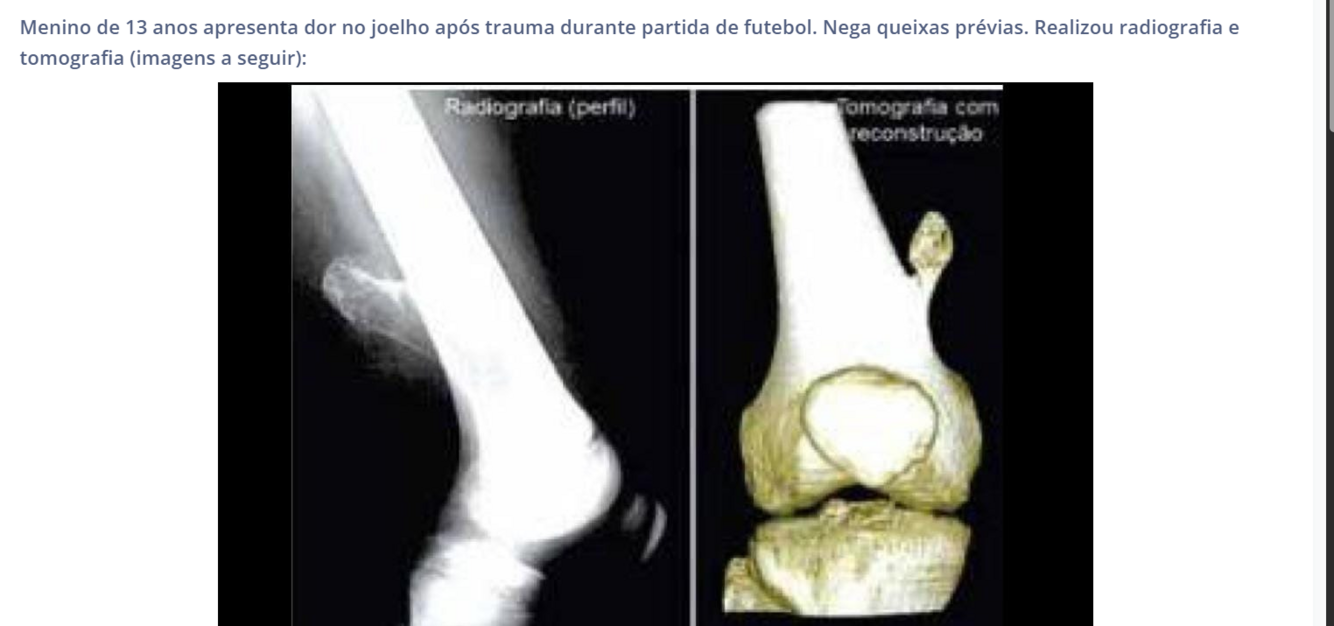

Lactente 8 meses, ivas previo, taquicardico, estertores crepitantes bilaterais e hepatoesplenomegalia.

Miocardite levando a insuficiencia cardiaca